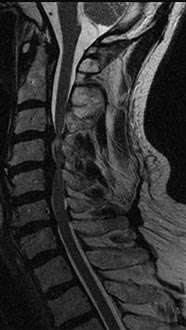

35 year old man presenting with severe neck pain with radiation down the right arm with right bicep weakness. MRI with large right C5-6 disc extrusion.

Postoperative xrays after C5-6 anterior cervical disc replacement. Complete resolution of arm pain and full painless range of motion of his neck.